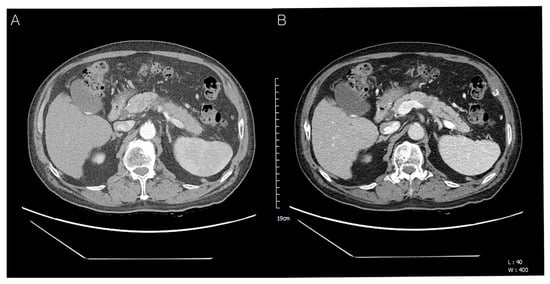

Figure 5. Abdominal CT findings post-operation, 10 months later. Ten months after the operation, the follow-up CT revealed a heterogenous enhancing mass (upper) in segment 8 of the liver with two previous RFA-treated hepatic masses (middle and lower) (A,B). After the third radiofrequency ablation for the new-developed hepatic mass, the patient is still alive.